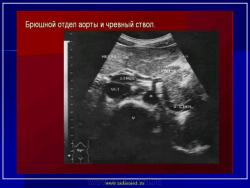

УЗИ  аорты.